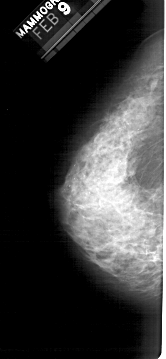

A_1196_1.RIGHT_MLO

RIGHT_MLO LINES 5281 PIXELS_PER_LINE 2656 BITS_PER_PIXEL 12 RESOLUTION 43.5 OVERLAY